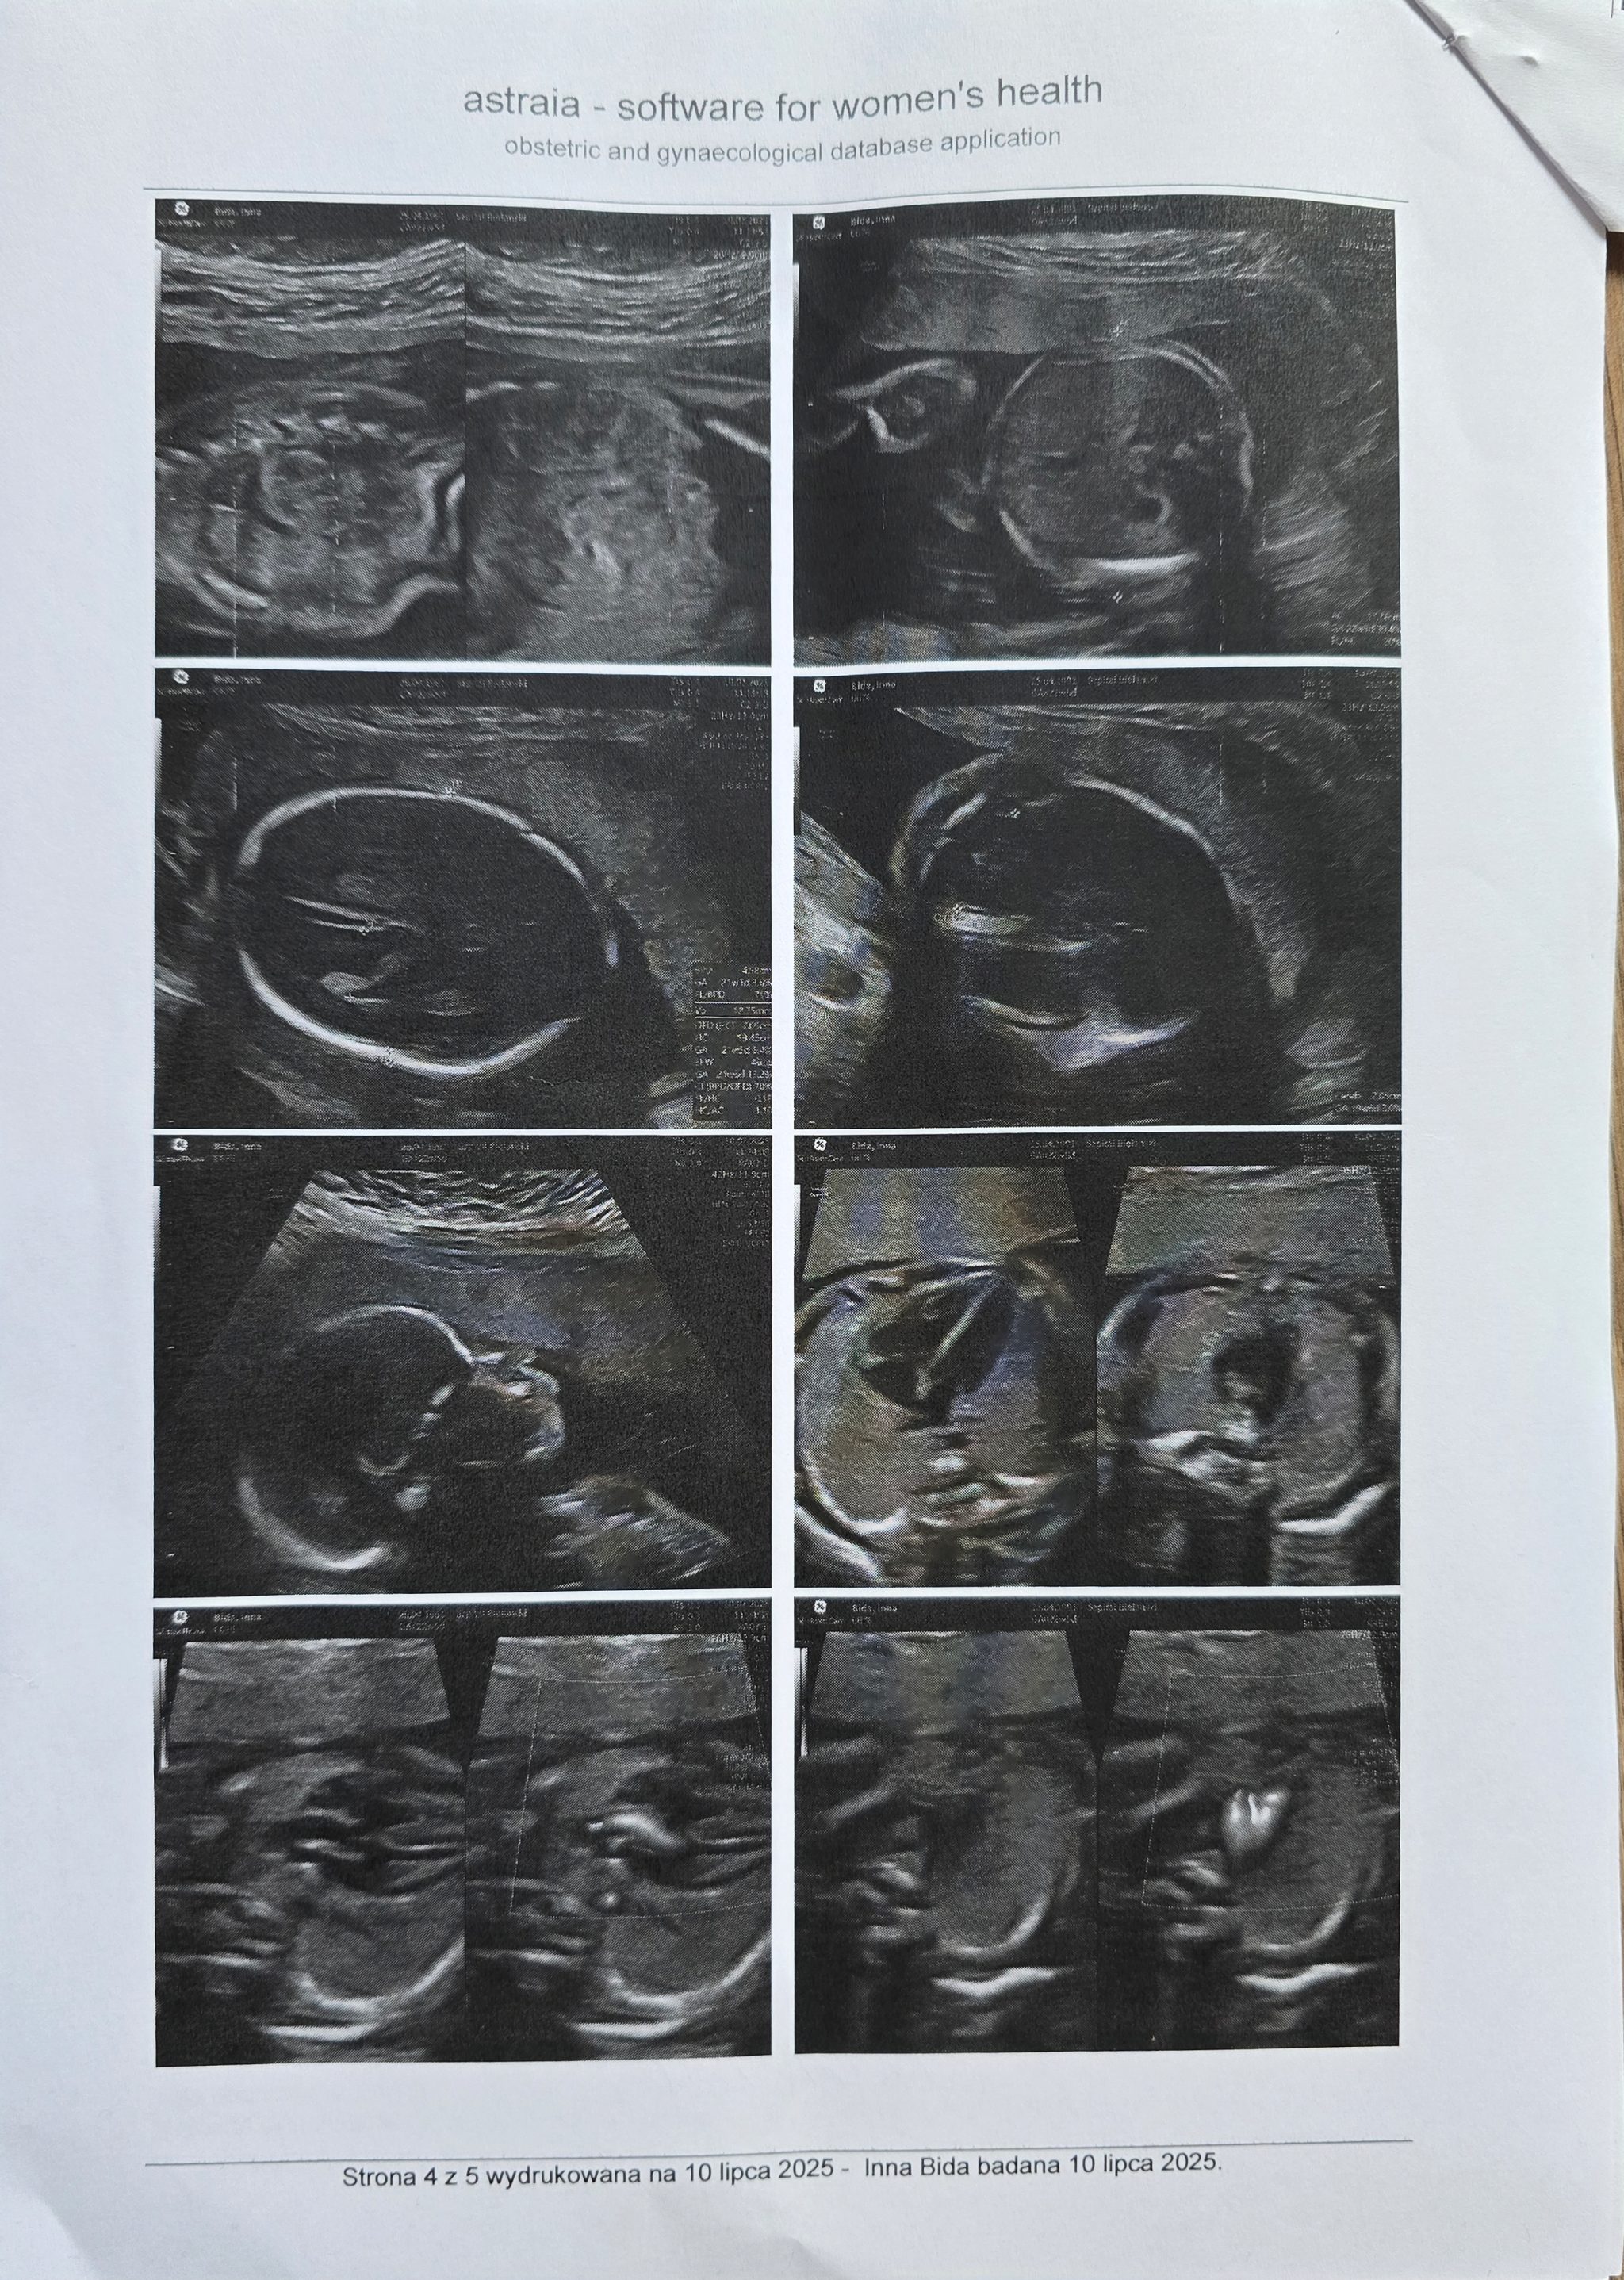

​Nasza walka o córeczkę zaczęła się, zanim jeszcze pierwszy raz zaczerpnęła powietrza. W 22. tygodniu ciąży usłyszeliśmy diagnozę, która brzmiała jak wyrok: otwarta przepuklina oponowo-rdzeniowa, czyli rozszczep kręgosłupa.

​Od tego momentu zaczęła się walka z czasem. W 25. tygodniu ciąży nasza malutka przeszła skomplikowaną operację wewnątrzmaciczną. Lekarze zamknęli rozszczep, dając jej szansę na lepszą przyszłość. To był cud współczesnej medycyny, ale to był dopiero początek naszej długiej i krętej drogi.